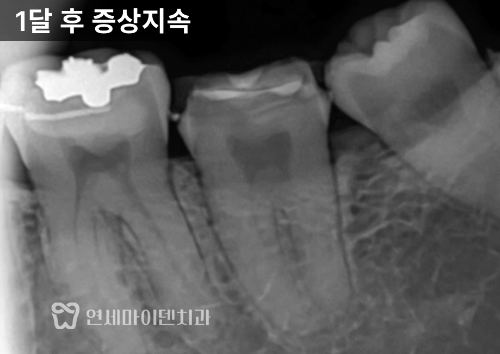

다만 크라운 치료 이후에도 한달이 지났는데도

증상이 여전히 남아있었습니다.

이런 경우 일반적으로는

전체 신경치료를 권유받는데요.

하지만 최근 떠오르는 생활치수치료(VPT)라는

치료법으로 신경을 살리는 방법도 있습니다.